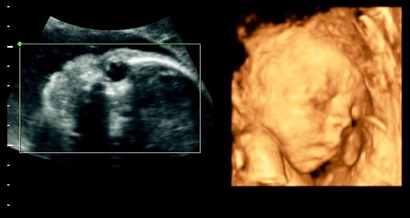

四维女宝宝特征有哪些?

1、孕囊大小看胎儿性别

有传言说,如果孕囊大小的长和宽的相差在一倍以上,那么男宝宝可能性大。长和宽相等,或者相差不大的话,很可能是个女宝宝。

2、孕囊形状看胎儿性别

有人认为,孕囊形状可以看出胎儿是男是女。一般说来,如果孕囊的形状像茄子,或者是呈长条状的,则怀上男宝宝的可能性大;而如果孕囊是椭圆形或圆形的,那么很可能就是个女宝宝了。